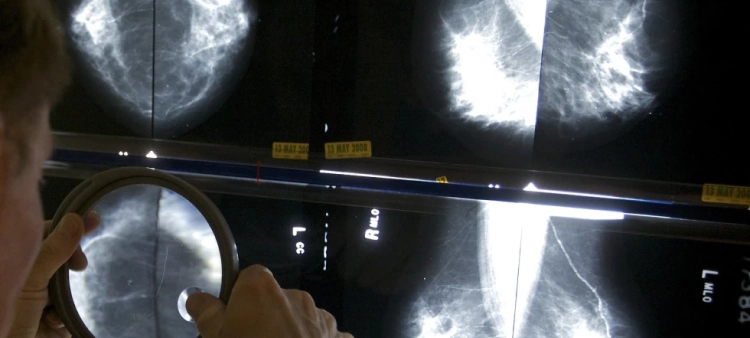

Bodies: Cuerpos Humanos Reales, abierta hasta el próximo 31 de octubre, exhibe ocho cuerpos humanos reales, cinco torsos y más de cien órganos y estructuras anatómicas.